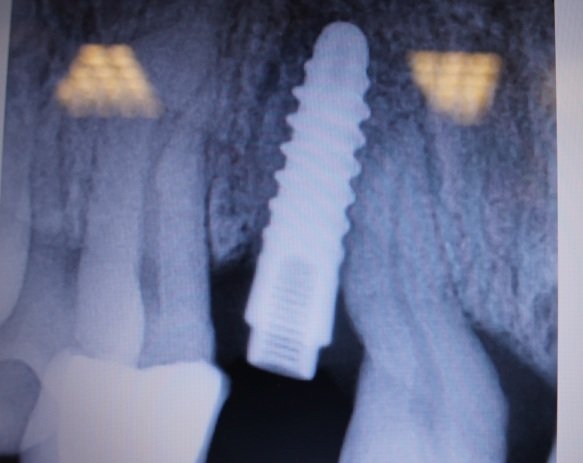

Necesito averiguar el tipo de implante de la siguiente radiografía.

No se que implante es.

aporto imagenes un abrtazo.gracias.